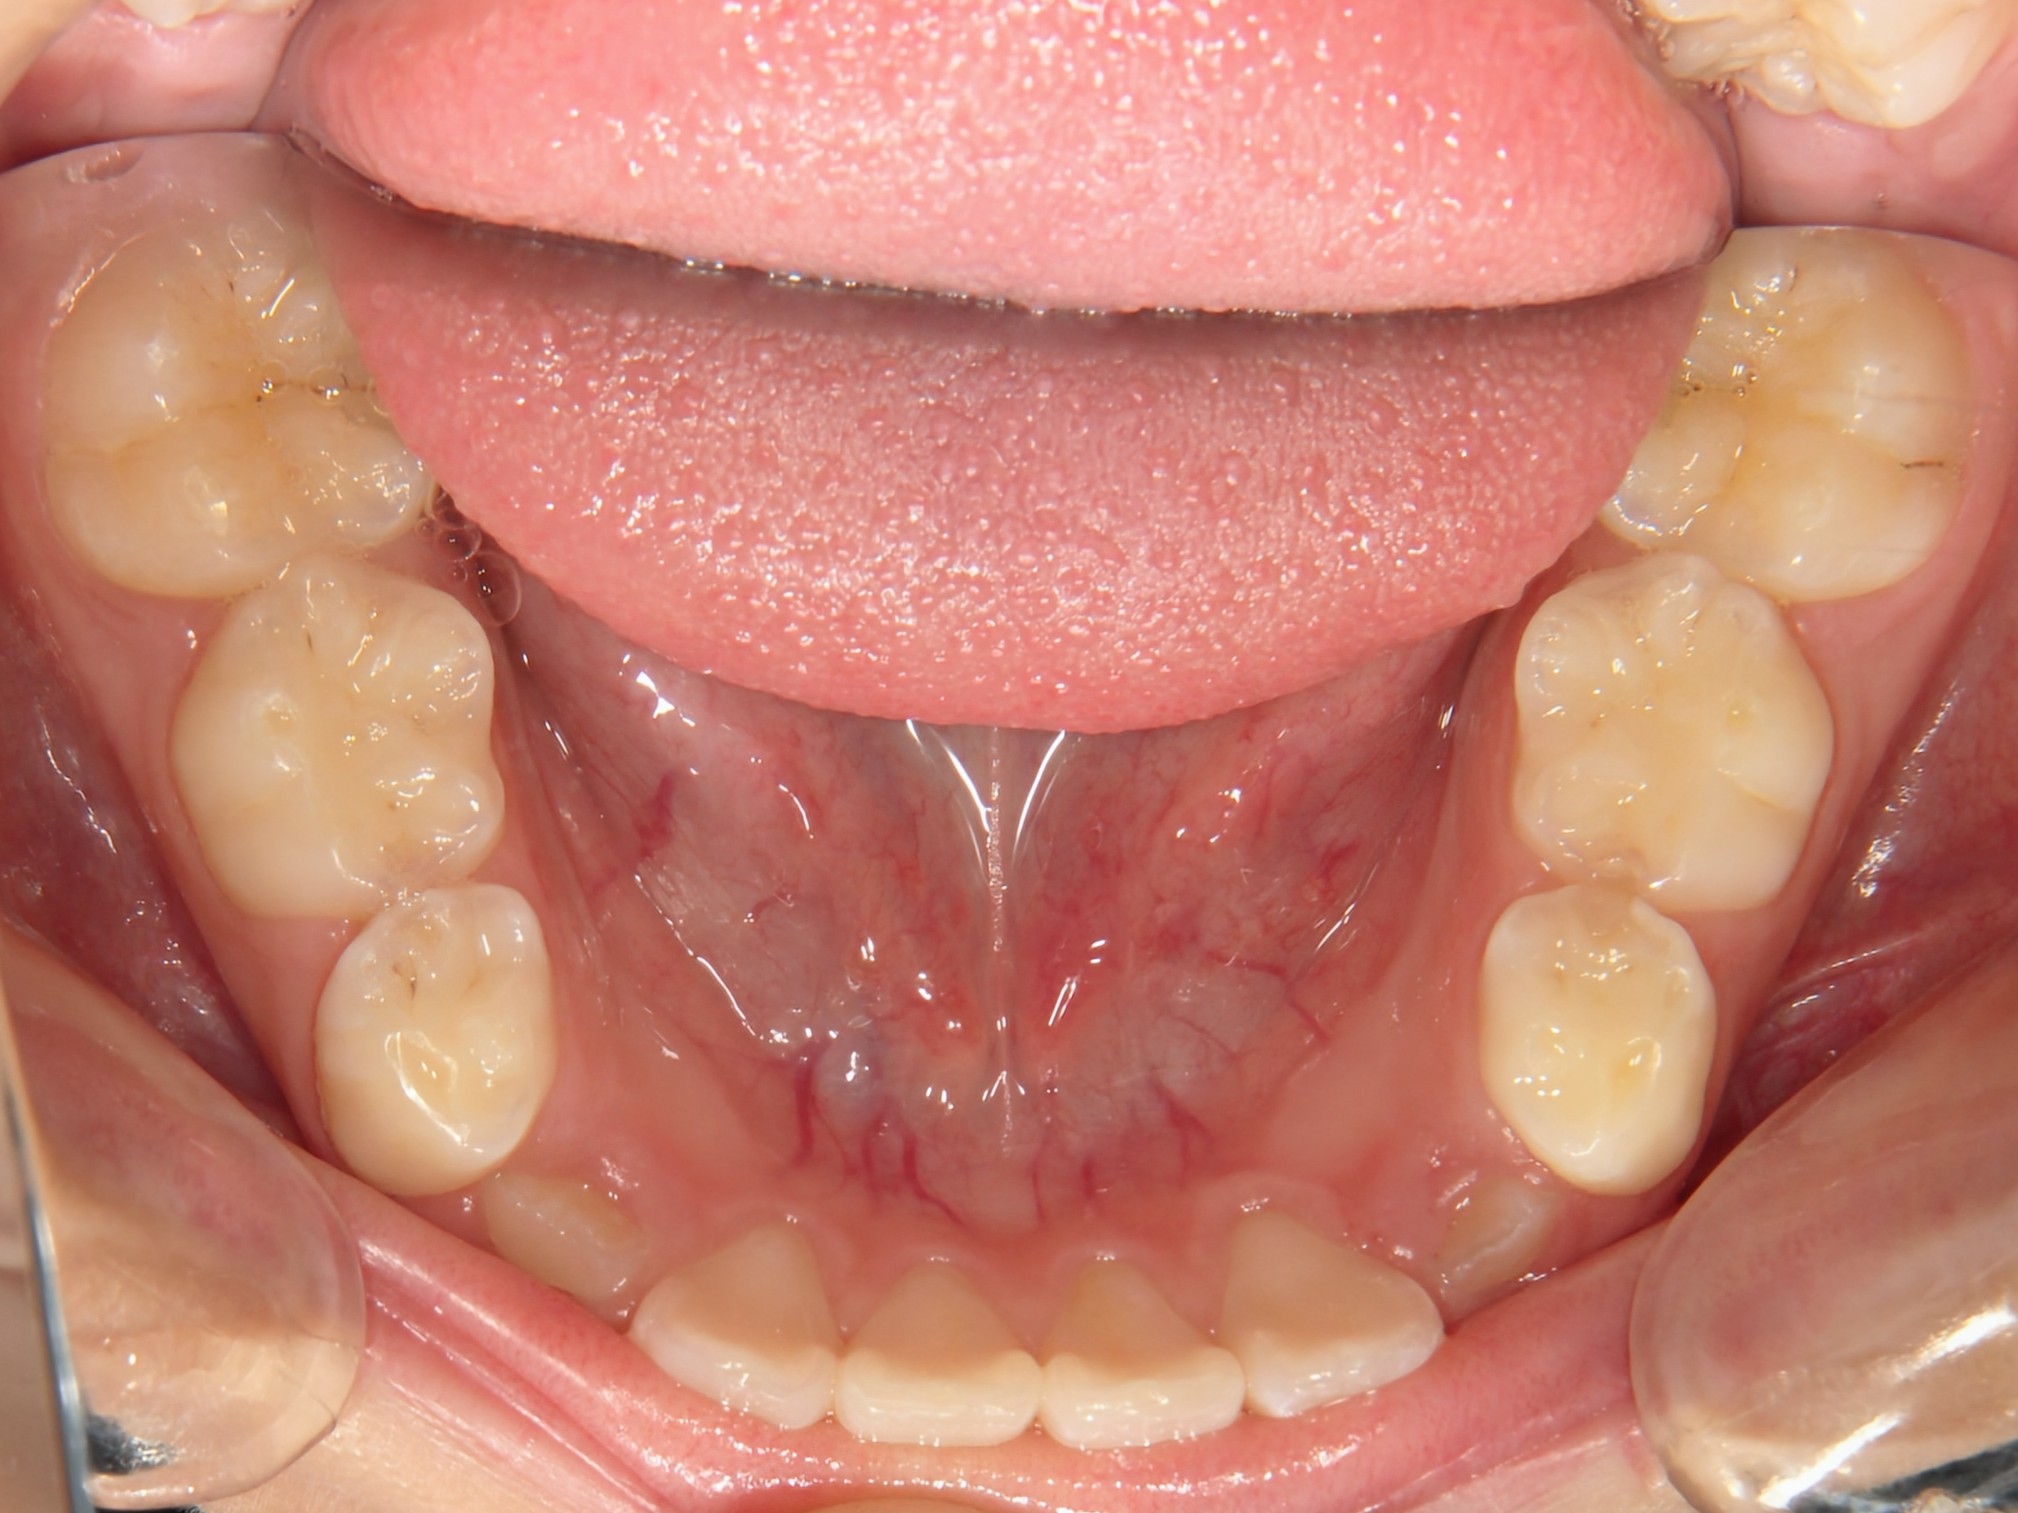

第2期治療終了時

顔貌写真

口腔内写真

治療結果

上下の歯のデコボコが改善

全体的な咬み合わせの緊密化

治療費(調整料含めて)

約95万円(第1期治療…40万円、第2期治療…55万円)

第1期治療期間

第1期治療開始:2021年8月

第1期治療終了:2022年1月

動的治療期間:5か月

第2期治療期間

第2期治療開始:2024年9月

第2期治療終了:2025年7月

動的治療期間:10か月

合計期間

3年10か月(動的治療期間:1年3か月+経過観察期間:2年7か月)

患者様は歯のデコボコを主訴で来院しましたが、第1期治療で歯列拡大+前歯部矯正を行ったことで、第2期治療で非抜歯矯正にて治療終了することができました。